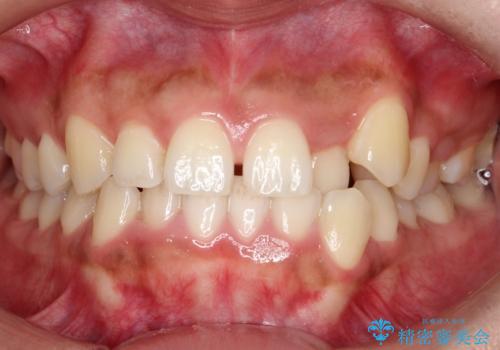

【非抜歯】インビザラインで正しい噛み合わせを

目立たない装置でデコボコを改善 ハーフリンガルによる矯正治療

前歯のガタつきを治したい 翼状捻転マウスピース矯正

八重歯とクロスバイト:インビザライン治療

非抜歯で短期間!ワイヤー矯正で理想の歯並びを実現